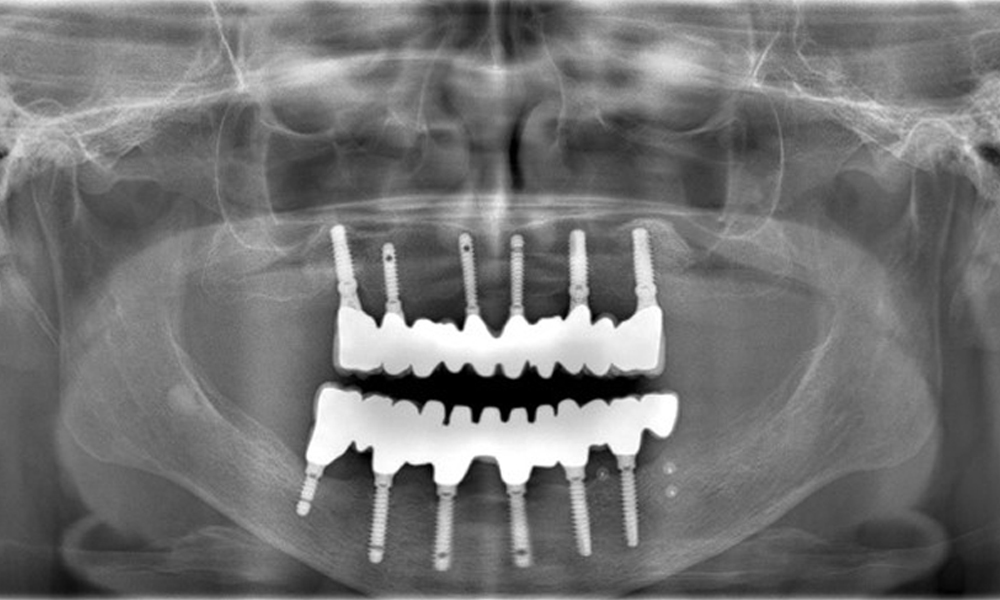

Eine 74-jährige Patientin stellt sich in der Sprechstunde vor. Die Anamnese zeigt, dass die Patientin gut eingestellten Bluthochdruck hat und Lixiana einnimmt. Weiterhin hatte die Patientin im Jahr 2020 ein Nierenkarzinom. Die Lebensgewohnheiten der Patientin sind unauffällig. Die Patientin hat keine eigenen Zähne mehr. Sie hat im Oberkiefer und Unterkiefer jeweils sechs Implantate, die mit Kronen bzw. über Brücken versorgt sind. Anhand der aktuellen Befunde lässt sich keine periimplantäre Mukositis bzw. Periimplantitis feststellen; vereinzelte (geringfügige) Blutungen an den Implantat(-versorgungen) liegen vor.

Versorgungen: Implantate regio 011, 013, 015, 021, 023, 025, 031, 033, 035, 042, 044, 046